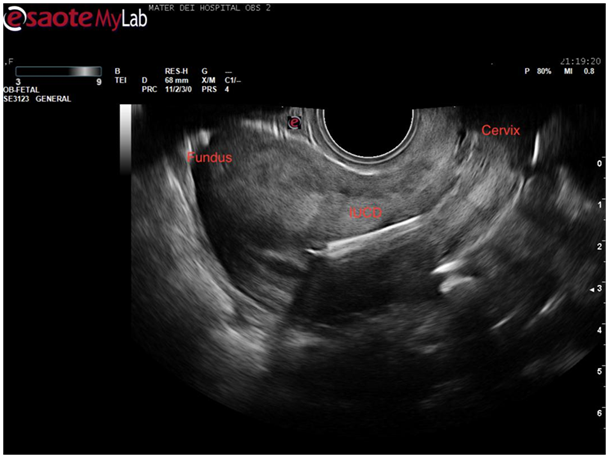

On placing the curvilinear probe on the patient’s abdomen a sagittal view of the uterus was obtained. The bladder was only slightly filled however a good view of the uterus, cervix, and vagina was obtained. Usually, in this view, the endometrial stripe is apparent. In this case, it became apparent that the uterus had a congenital anomaly as 2 horns were clearly visible (Figure 1).

Figure 1 Trans abdominal ultrasound showing a sagittal view of the uterus. Two horns are apparent with a possible gestational sac in the left horn.